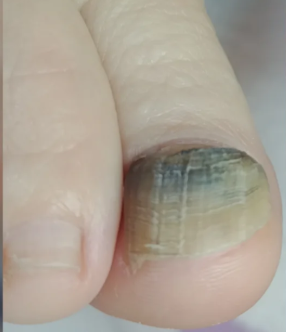

Onicomicosis (hongo)

Onicomicosis (hongo)

- Onicomicosis (micosis en uñas)